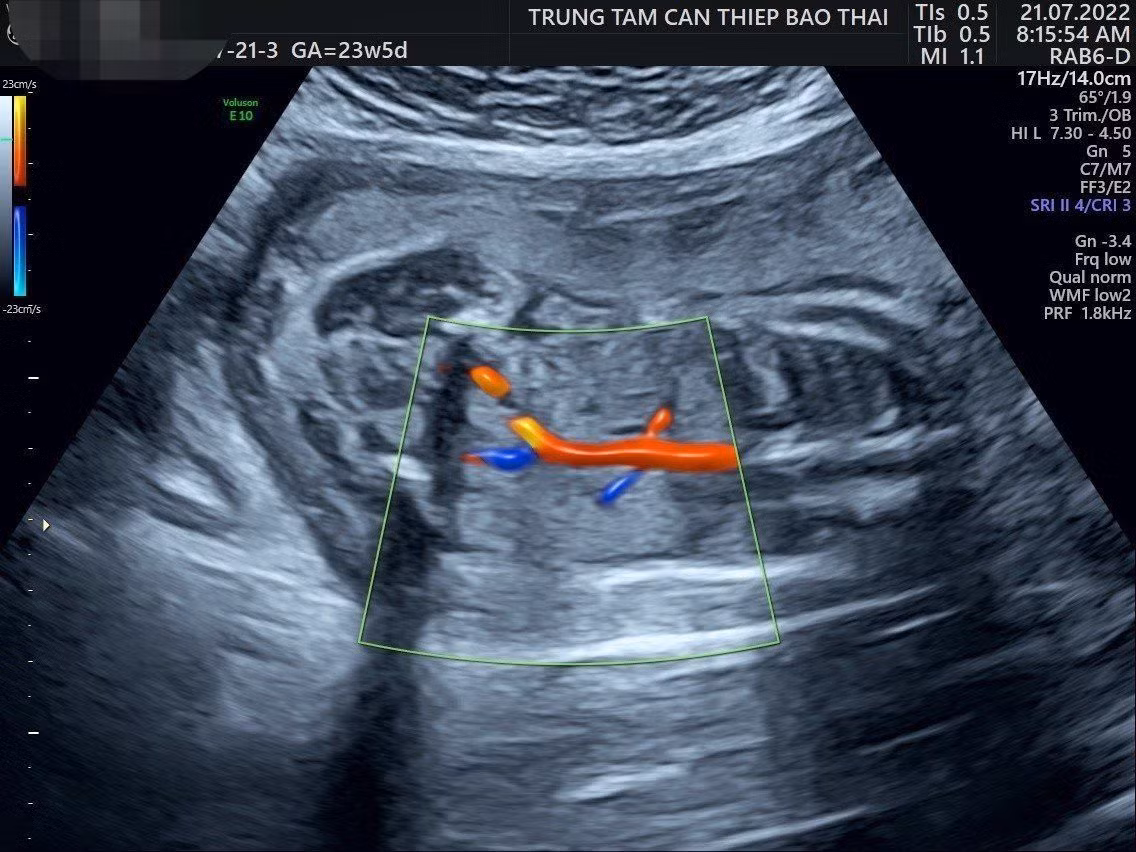

![]() |

| Hình ảnh siêu âm hình thái bào thai của sản phụ O. |

“Sản phụ đến ở tuần 20, không bị ra nước âm đạo, không có dấu hiệu vỡ tử cung mà nước ối “tiêu” hết. Chúng tôi loại trừ hết nguyên nhân từ mẹ, từ bánh rau vì tuần hoàn tử cung tốt, thai tăng trưởng, không rách vỡ màng ối. Trên siêu âm, thấy hết ối, thai bị bó chặt không kết luận được một cách đầy đủ nhất bất thường về hình thái. Hình thái 2 thận của thai vẫn rõ, không có nang hay loạn sản rõ ràng trên siêu âm, chỉ thấy không có nước tiểu trong bàng quang thai nhi nên nghĩ chức năng thận thai bất thường.

Vừa là bác sĩ chuyên sâu về sản khoa y học bào thai đồng thời là tiến sĩ di truyền nên với kinh nghiệm lâu năm, bác sĩ Sim nghĩ tới 2 tình huống: tử cung cạn ối có thể là hậu quả lâu ngày sản phụ uống ít nước hoặc có thể bệnh thận của bào thai gây ra mất nước ối, không sản sinh nước tiểu. Và tình huống thứ 2 được nghĩ tới nhiều hơn là bào thai không thấy dấu hiệu tiết nước tiểu vào bàng quang, dù vẫn có thận và mạch nuôi thận.

Nhiệm vụ “2 trong 1” vừa chẩn đoán, vừa điều trị được vạch ra trong lần truyền ối bào thai này. Bác sĩ Sim cho hay, nhiệm vụ lớn nhất là truyền ối để em bé có nước ối tăng trưởng dễ dàng. Nhưng nhiệm vụ quan trọng nhất là có đủ ối để siêu âm chẩn đoán đánh giá lại xem bào thai có bất thường về hình thái không, xem thận hoạt động thế nào khi có nước ối.

Thai phụ được tiến hành bơm 500ml dung dịch Ringer lactate vào buồng ối, sau đó hút dịch ối ra để thực hiện xét nghiệm di truyền. “Các phát hiện từ siêu âm chẩn đoán hình thái sau bơm ối không thật sự mang lại kết quả như kì vọng của bệnh nhân. Vì sau truyền ối vẫn không thấy nước tiểu trong bàng quang thai nhi, chứng tỏ hệ tiết niệu của thai không hoạt động. Chúng tôi kiên nhẫn chờ đợi 1 giờ, 24 giờ, thậm chí cả một tuần sau để xem có phép màu ở bào thai hay không thì thực tế, nước tiểu vẫn không từ thận xuống bàng quang. Chúng tôi vô cùng buồn, không thể có được một giải thích thấu đáo cho sản phụ”, bác sĩ Sim buồn bã nói.